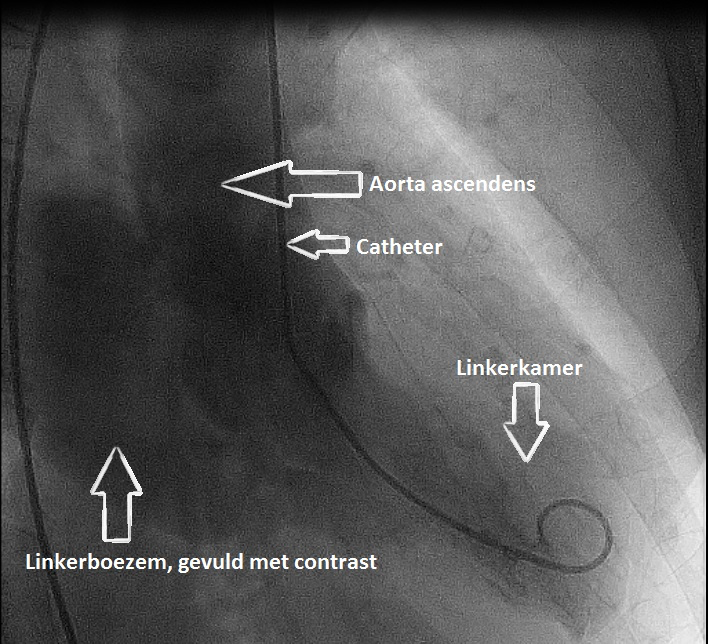

Video 3 linkerventrikelangiografie